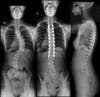

Image shows before and after Isabella’s scoliosis surgery

Despite the brace, her condition was not improving. Not only did Isabella have back problems as a result of adolescent idiopathic scoliosis, but it was affecting her ribs and internal organs. Carolina says it progressed so much that her spine looked like an S.